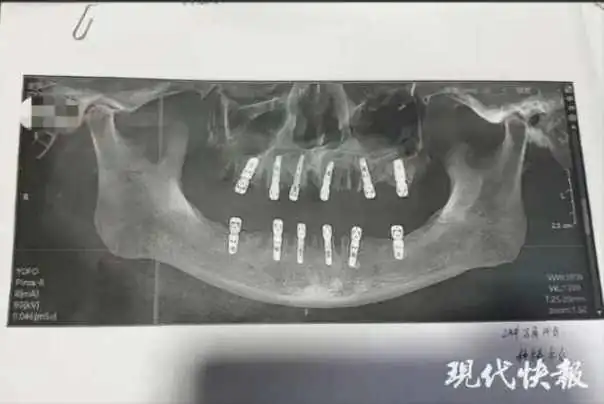

Šu tvrdi da je njenom ocu tokom jedne posete izvađeno 23 zuba i ugrađeno 12 implantata, što je, prema njenim rečima, dovelo do njegove prerane smrti 13 dana kasnije.

U obrascu za pristanak pacijenta, navodi se da je pacijent prvo imao 23 vađenja prirodnih zuba, a zatim su mu izbušene rupe u lobanji i donjoj vilici za postavljanje implantata, sve u jednom danu.